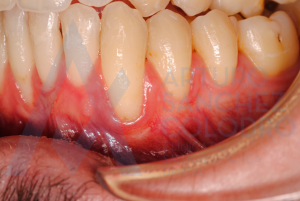

Aquí puede observarse la colocación de la membrana regenerativa

Tras la cirugía mucogingival realizada por el Dr. Arturo Sánchez Colodro en la primera parte de la boca (paciente aún en fase de tratamiento):